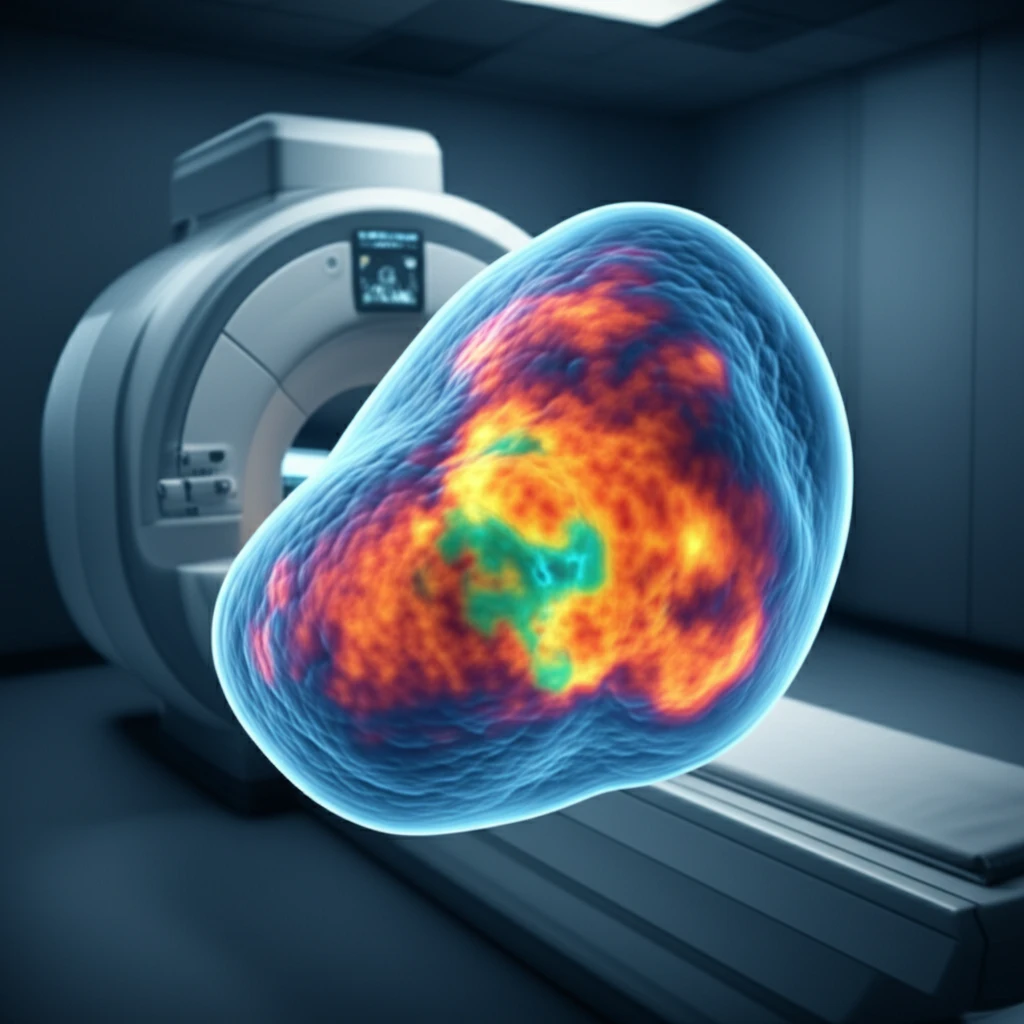

Traditional imaging techniques like X-rays and CT scans offer valuable insights, magnetic resonance imaging (MRI) has emerged as a powerful tool for visualizing soft tissue tumors. MRI provides detailed anatomical information and can differentiate between different types of tissues. However, standard MRI sequences sometimes fall short in characterizing tumors fully.

Apparent diffusion coefficient (ADC) mapping, a technique that enhances MRI, has emerged as a valuable tool in the diagnosis and management of soft tissue tumors. ADC mapping measures the diffusion of water molecules within tissues, providing information about cellularity and tissue structure. This information can help differentiate between benign and malignant tumors and assess treatment response.

ADC mapping works by measuring the movement of water molecules within tissues. In highly cellular tissues, such as tumors, water diffusion is restricted due to the presence of cell membranes and other cellular components. This restriction results in lower ADC values. Conversely, in tissues with less cellularity or increased extracellular space, water diffusion is less restricted, leading to higher ADC values.